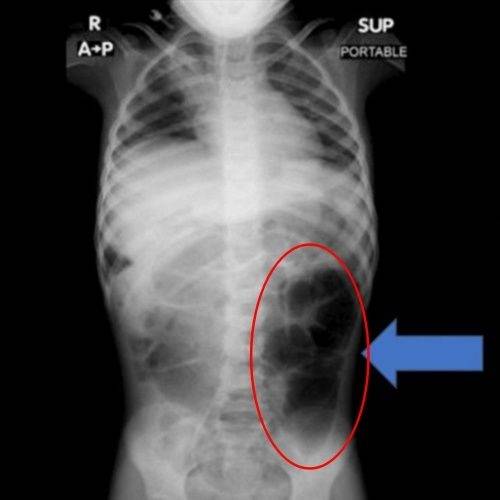

23일 의학 저널 큐레우스(Cureus)에 따르면 사우디아라비아에 거주하는 6살 여아 A양은 복통과 소화 장애 증상이 수주간 지속돼 병원을 찾았다. 단순한 위장 장애로 여겨졌던 증상은 정밀 검사 결과 예상치 못한 원인으로 드러났다.

검사 결과 A양의 위 내부에서는 비정상적으로 큰 이물질이 발견됐고, 의료진은 즉각 수술을 결정했다. 제거된 이물질은 다량의 머리카락이 엉켜 형성된 덩어리로, 위에만 머무르지 않고 소장의 일부까지 길게 이어진 상태였던 것으로 확인됐다.

의료진은 “소아 환자에게서 반복적인 복통이나 구토, 식욕 저하가 장기간 지속될 경우 위장관 내 이물질 존재 가능성을 반드시 고려해야 한다”며 “영상 검사를 통한 조기 진단과 신속한 치료가 매우 중요하다”고 강조했다.

이 같은 질환은 '라푼젤 증후군'으로 불린다. 머리카락을 뽑아 먹는 습관인 발모식증이나 모발섭식증으로 인해 위 속에 머리카락 덩어리가 형성되고, 이것이 소장까지 길게 이어지는 매우 희귀한 질환이다. 동화 속 라푼젤처럼 머리카락이 길게 늘어진 모습과 닮았다는 점에서 이름이 붙여졌다.

라푼젤 증후군은 주로 청소년과 젊은 여성에게서 나타나며, 불안·강박·스트레스 등 심리적 요인과 동반되는 경우가 많다. 주요 증상으로는 복통과 복부 팽만, 구토, 소화불량, 체중 감소, 식욕 부진 등이 있으며, 심한 경우 장 폐색이나 출혈, 장 천공으로 이어질 수 있다.